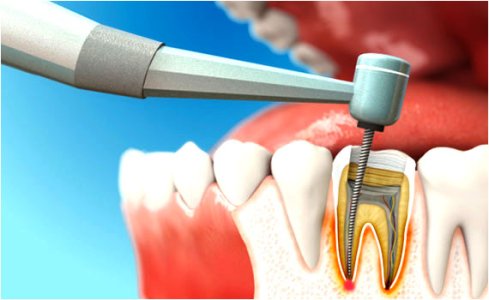

Каналы корней зуба — это анатомические пространства внутри зубных корней, заполненные пульпой. Соединены мелкими ответвлениями между собой и с поверхностью зубного корня. Число каналов зависит от расположения зубов: у резцов и клыков один корень, у премоляров количество может увеличится до двух, у моляров их число достигает 3-4 штук, а у зубов мудрости фиксируется даже пять корней. Основными заболеваниями корневых каналов являются хронические и гнойные пульпиты. Лечение может проводиться при помощи противовоспалительных лекарственных препаратов и удаления сосудисто-нервных пучков.